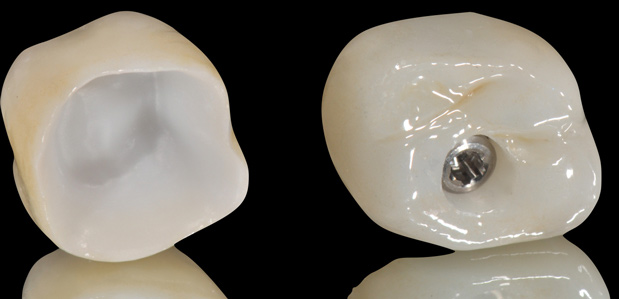

Unfortunately, randomized clinical trials for fully digitalized workflows for either teeth or implant-supported fixed restorations are scarce. Presently, a strong offering of rapid prototyping procedures exists, including CAD/CAM-produced full-contour or monolithic crowns (Figure 24) and milled frameworks combined with CAD/CAM veneering superstructures. A true digital workflow for crown-and-bridge is not mainstage at present, and barely exists in an analog-digital blend, but the authors believe this will change soon. The layering of porcelain is cumbersome and operator dependent with many working parts and lacks the consistent precision found with today's computerized technology. Joda described a threefold improvement in time efficiency, and either no or minor adjustments of implant-supported crowns, using a digital workflow (intraoral scanning and CAD/CAM technology) in comparison to conventional methods.20 Laboratory time savings have been most impacted by the digital workflow (average 54.5 minutes of production time versus 132.5 minutes), along with a 30% overall treatment cost reduction.21

Fig 16. Presurgical design and fabrication of restorative components based on virtual implant position, allowing for possible minor angle/linear deviations (Fig 16 through Fig 18). Component options are broad and may include a custom healing abutment and bondable polymethyl methacrylate restoration; a single restoration with an engaging or non-engaging base; provisional fixed partial dentures (Fig 19), which can be indexed intraorally to prepared temporary abutments; or a full-arch restoration to be indexed intraorally to prepared temporary abutments.

Fig 17. Presurgical design and fabrication of restorative components based on virtual implant position, allowing for possible minor angle/linear deviations (Fig 16 through Fig 18). Component options are broad and may include a custom healing abutment and bondable polymethyl methacrylate restoration; a single restoration with an engaging or non-engaging base; provisional fixed partial dentures (Fig 19), which can be indexed intraorally to prepared temporary abutments; or a full-arch restoration to be indexed intraorally to prepared temporary abutments.

Fig 18. Presurgical design and fabrication of restorative components based on virtual implant position, allowing for possible minor angle/linear deviations (Fig 16 through Fig 18). Component options are broad and may include a custom healing abutment and bondable polymethyl methacrylate restoration; a single restoration with an engaging or non-engaging base; provisional fixed partial dentures (Fig 19), which can be indexed intraorally to prepared temporary abutments; or a full-arch restoration to be indexed intraorally to prepared temporary abutments.

Fig 19. Presurgical design and fabrication of restorative components based on virtual implant position, allowing for possible minor angle/linear deviations (Fig 16 through Fig 18). Component options are broad and may include a custom healing abutment and bondable polymethyl methacrylate restoration; a single restoration with an engaging or non-engaging base; provisional fixed partial dentures (Fig 19), which can be indexed intraorally to prepared temporary abutments; or a full-arch restoration to be indexed intraorally to prepared temporary abutments.

Fig 24. Full-contour monolithic crowns for teeth and implants constitute the last phase of the digital workflow.

Figure 24